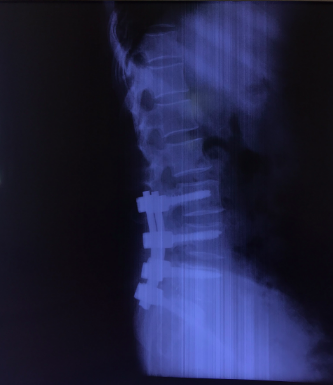

Bệnh nhân Nguyễn Thị T. (53 tuổi) tại Nghi Thuỷ - TX Cửa Lò xuất hiện tình trạng đau cột sống thắt lưng đã lâu, được điều trị bằng Y học cổ truyền và Phục hồi chức năng nhiều năm nay. Hiện tại, tình trạng đau tăng lên, đau tê dọc 2 chân, đi lại khó khăn, cơ lực 2 chân giảm. Sau khi tìm hiểu tham khảo nhiều đơn vị khác, chị T. được giới thiệu tới bệnh viện CTCHNA thăm khám và được chẩn đoán trượt đốt sống thắt lưng L5 độ III, thoát vị đĩa đệm L5S1 gây hẹp ống sống nặng, chèn ép rễ thần kinh L5 hai bên.

Hình ảnh: Cộng hưởng từ và X Quang bệnh nhân trước phẫu thuật